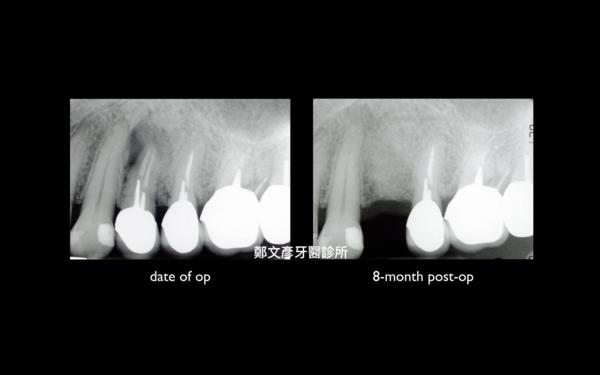

Role of granulation tissue in socket preservation

3. Role of granulation tissue in socket preservation